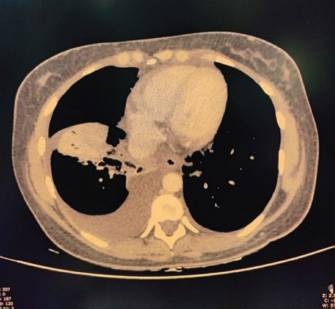

USG’s whole abdomen revealed hepatomegaly and mild to moderate ascites. In view of melena and thrombocytopenia, 6 units of random donor platelets were transfused. A workup for fever with thrombocytopenia and polyserositis was started. Dengue RTPCR, NS1 antigen, IgM, Weil felix, and VDRL were negative. Viral markers (HIV/HBsAg/Anti HCV/Anti HAV IgM/Anti HEV IgM) were negative. Scrub IgM, Brucella IgM, Urinary legionella antigen, CMV PCR, and Leptospira IgM were negative. Malaria Ag and P/S for the malaria parasite were negative. The widal test and Typhidot IgM were negative. CPK and CK-MB were negative. Stool occult blood (three samples) were negative. Covid PCR was negative. Blood and urine C/S were negative. Urine KOH revealed few budding yeast cells. Urine fungal culture was negative. Workup for EBV revealed 24,300 copies of EBV RTPCR and EBV IgM and IgG were positive. We did an autoimmune workup considering a young female with polyserositis but both ANA by Immunofluorescence and ANA profile were negative. Direct and indirect Coombs tests were negative. By the end of first week of admission, thrombocytopenia started improving but she had a persistent cough and fever although spikes were reduced. A 2D echo revealed trace pericardial effusion. Repeat Chest X-ray revealed persistent bilateral pleural effusion (Right > Left) (Fig. 2). In view of persistent effusion, we decided to perform a CECT chest and abdomen which revealed evidence of moderate right pleural effusion, minimal fluid in the left pleural cavity with atelectatic changes in the adjacent lung, oedematous thickened gallbladder and mild ascites (Figs. 3 and 4).

Fig. 4. CECT abdomen suggestive of edematous thickened gall bladder and mild ascites.